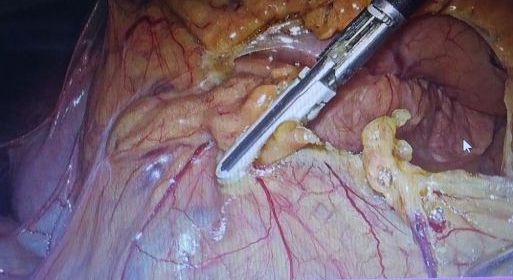

诊断:1.胃癌,性质待病理;病理活检,胃镜病理示:(胃体)粘膜轻度慢性炎,中度萎缩,部分腺体高度异型增生,局部呈腺癌改变。处理:完善辅检后行腹腔镜胃癌根治术,术中注意肝十二指韧带及脾门区血管解剖,这样才不会导致术中操作不当的出血。遵循正确的手术方法。遵循术中清扫步骤,首先要暴露脾门区,其次裸化胃网膜左血管和裸化脾动脉,最后裸化脾叶动脉。处理好术后的并发症。肝十二肠韧带及脾门淋巴结清扫最容易发生的并发症是引起血管的损伤,脾被膜的损伤,引起出血,术中控制不了出血的话只能进行脾切除,本例手术顺利。术后胃肠外营养,抗感染,补液。术后7天治愈出院。

术后随访3个月无异常。讨论:腹腔镜胃癌手术具有疼痛轻、创伤小、恢复快等优势,已逐渐被广大外科医师所接受,开展的单位也越来越多。如何进一步规范腹腔镜胃癌手术,提高其操作水平是目前亟待解决的重要问题。严格把握手术适应证,规范腹腔镜胃癌手术操作流程,建立规范的培训体系为其推广提供技术保障,做好腹腔镜胃癌手术患者围术期处理,将加速康复理念应用于腹腔镜胃癌手术患者,将使患者更好地获益。